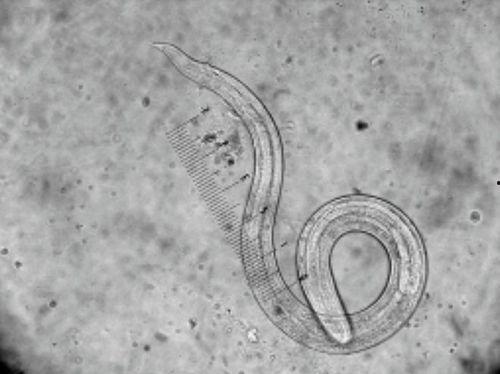

寄生虫的种类繁多,有原生动物、蠕虫、节肢动物等。它们通过吸取宿主的营养来维持生命,有时还会引发各种疾病。那么,这些寄生虫是如何进入我们的身体的呢?

2. 蛔虫病:由蛔虫引起,主要通过食用被污染的食物或水源传播。蛔虫病会导致营养不良、腹痛、腹泻等症状。

3. 钩虫病:由钩虫引起,主要通过接触感染了钩虫的土壤传播。钩虫病会导致贫血、营养不良、皮肤瘙痒等症状。